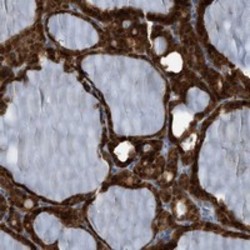

- Experimental details

- Immunohistochemical staining of human thyroid gland with C21orf57 polyclonal antibody (Cat # PAB21140) strong cytoplasmic positivity in glandular cells at 1:200-1:500 dilution.

- Validation comment

- Immunohistochemistry (Formalin/PFA-fixed paraffin-embedded sections)